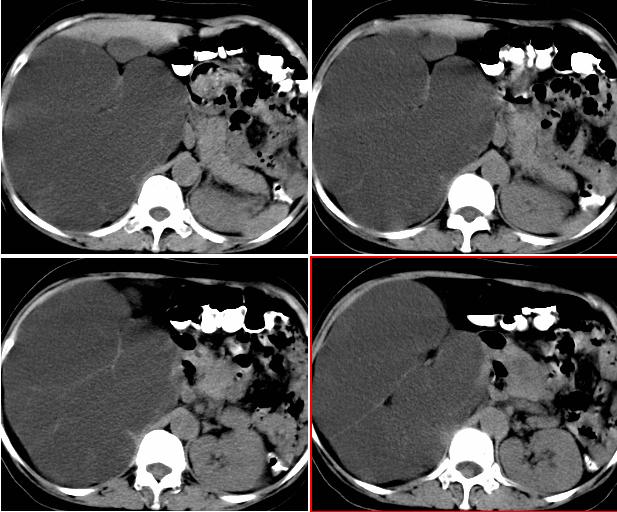

右侧后腹膜巨大囊性肿块影阴,边缘清晰,内见膜状分隔,均匀水样密度,右肾影阴消失,囊块所到区域脏器受挤移位,右侧输尿管扩张,应该考虑:右肾重读积水,巨大肾囊肿不除外。引发肾性高血压。

从囊性低密度区的形态,及分布看我支持1楼战友的分析及诊断意见。{右恻输尿管全程扩张,阻塞位置应该在输尿管与膀胱的交界区,建议行膀胱镜检,楼主还是应该给患者作强化扫描!!!!!}

腹部巨大囊性占位,膨胀性生长,边界光整,囊内容物为水样密度,其内可见多发分隔,右恻输尿管全程扩张,纵观所有层面,正常右肾未见,考虑为来源于右肾的巨大多房性肾囊肿可能性大。

反推一下:1.那么重的积水,引起积水的原因大部分是右侧输尿管有梗阻,排出受阻。右侧输尿管应该也是重度扩张才对。2.如果是肾积水,而且是右侧输尿管问题引起,那么病人肯定有相应的临床症状:比如输尿管结石引起的血尿、剧痛等症状,至少也会急性发作病史。另,本例显然不需要考虑输尿管癌,膀胱也挺好,更没有无痛性血尿病史。病人8年多没有其他的不舒服,只是腹部日渐膨隆,临床症状显然不支持。3.如果是重度肾积水的话,应该可以看到被压缩的肾皮质,即使很菲薄也多少会有显示的。

右输尿管肾盂肾盏高度括张扭曲,第三狭窄处或周围应见结石或其他原因梗阻。考虑先天畸型,如重复畸形。

右肾明显扩大,皮质菲薄,间隔细,右输尿管全程扩张,右肾重度积水,原因应重点查输尿管膀胱接合处。